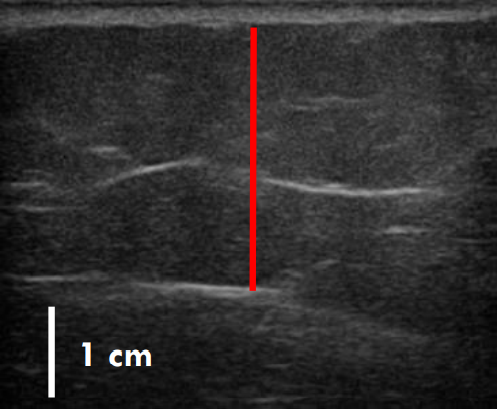

실제 지방이 어느 정도 감소했는지는 초음파 사진을 보면 더욱 뚜렷하게 확인할 수 있는데.

트루스컬프ID 시술 전, 12주 후

초음파를 비교한 사진입니다.

레드 라인이 지방층의 두께입니다.

앞서 보여드린 사례의 경우 시술 전과 비교했을 때 약 36% 정도 지방이 감소한 결과를 볼 수 있는데요.

이 정도의 지방량을 줄이려면 일반적인 운동, 식이요법만으로는 한계가 있지요.